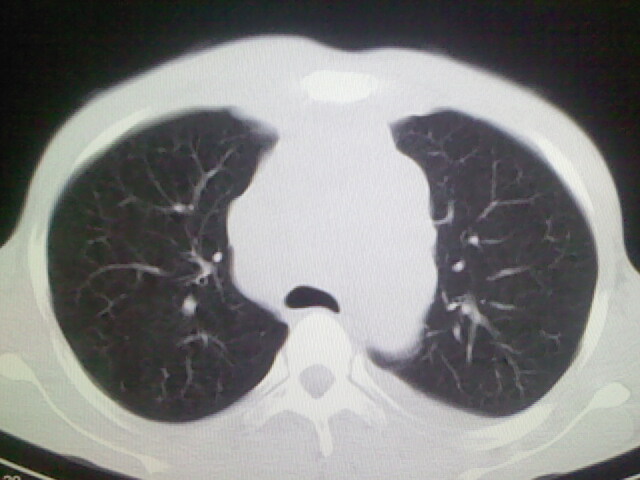

以下是引用杀毒软件在2008-9-3 6:11:00的发言:[br]侵袭性胸腺瘤------一般不侵到气管旁[br][br]考虑----纵隔淋巴瘤,心包及胸膜受累

以下是引用wzr在2008-9-3 5:30:00的发言:[br]侵袭性胸腺瘤

以下是引用随光逐影在2008-9-3 7:07:00的发言:[br]1)考虑淋巴瘤可能。2)双侧胸腔积液(以左侧为甚)。3)心包积液。